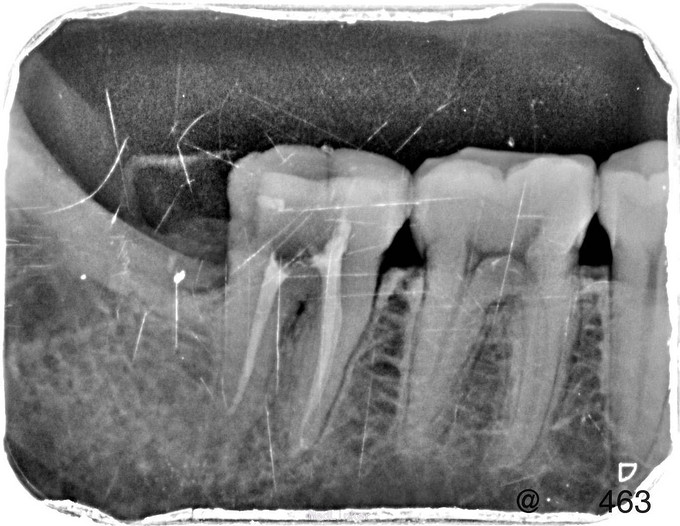

临床检查:48未完全萌出,盲袋附着无溢脓,47合面无明显龋坏,远中邻面探(++),冷(++),叩(-),松动度(-),牙周正常. 辅助检查:X线示48近中阻生,47龋坏累积髓腔,根尖周牙周膜增宽。

诊断:47牙髓炎,48阻生齿。 治疗:经患者知情同意后,47局麻去腐降牙合,开髓拔髓寻找根管口,建立直线通路,扩通根管,确定工作长度。S3/EDTA凝胶镍钛器械,低浓度次氯酸钠冲洗根管,预备至25/06,氢氧化钙诊间封药,48翻瓣拔除,缝合。一周后复诊,试主尖X线示恰充,试干根管,导AH-PLUS糊剂,热压胶垂直加压根充,术后见根管恰充,暂封观察嵌体修复。拔牙创拆线。